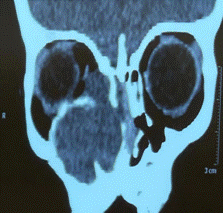

此例患者年龄为1岁3个月,右侧面部隆起,眼球突出,1个月内进展迅速,为婴儿罕见病例。患儿及家属辗转于省内多家医院,最终入住西安交通大学第一附属医院耳鼻咽喉头颈外科,权芳主任医师带领的团队在经全科讨论后,最终制定了以手术为主的治疗方案。由于患儿年龄小,且肿瘤范围大,血供丰富,有效循环血量仅800ml,术中出血成为最为关注的问题,且止血难度极大,术后感染不易控制,患儿配合差。术前在权芳主任医师的组织下进行了多学科(影像科、眼科、血管外科、麻醉科、中心ICU、新生儿科等)会诊讨论,对患者的术前评估、手术方式、手术可能出现的并发症、术后处理措施及围手术期患者的全身管理及护理等方面做了充分的准备,并制定了多种意外情况下的备用方案。

术后病理报告为富含粘液及血管的间叶源性肿瘤,经免疫组化和二代全基因测序,诊断为世界罕见的婴儿原始黏液样间叶性肿瘤,目前世界范围内共计报道30余例,多数患儿预后差,完整切除为首选治疗方案,化疗效果不确定,尚无统一指南建议。因此准确及时的诊断及手术至关重要,对该肿瘤的生物学行为和预后的明确认识还有赖于长期随访和更多病例的积累。